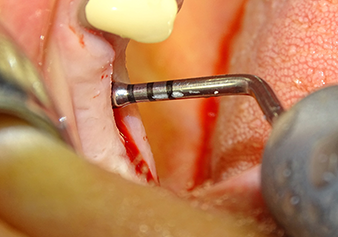

После промежуточного контроля (рис. 4) был проведен еще один этап подготовки (рис. 5). За тем, с помощью гидравлического инструмента Z35P мембрана была поднята в нужное положение (рис. 6 и 7). Далее, следовала дальнейшая пьезохирургическая подготовка ложа для имплантата, завершенная с помощью ротационного бора и лопаточной фрезы до диаметра имплантата 4,8 мм. Перед установкой имплантата под мембрану Шнейдера был введен аугментационный материал (размер частиц около 0,8-1,6 мм) (рис. 8).